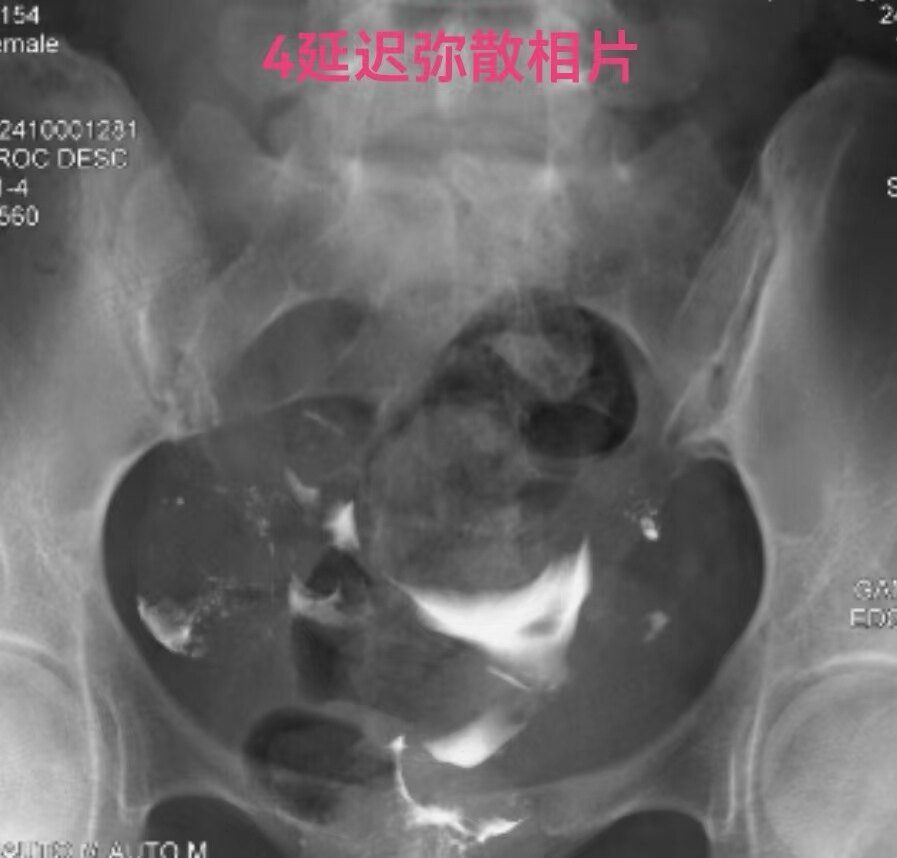

在做子宫输卵管造影检查时:当所用造影剂为碘油,出现静脉和淋巴管逆流时,立即停止造影检查是对的。因为碘油和血液不能相容混合一起,碘油会形成油栓。因此,当碘油进入静脉和淋巴管后会进入下腔静脉,进入右心房,进而进入肺动脉,形成肺栓塞,可危机被检查者生命安全。但是,当所用造影剂为碘水,出现静脉和淋巴管逆流时,可以继续造影检查,直至满足临床诊断后再结束检查。因为碘水和血液可以相容会混合一起,碘水逆流进入静脉和淋巴是安全的。大家好多做过CT增强检查,成年人一般需要用高压注射器要向静脉内快速注入100毫升碘水进行检查,都是安全的。造影注入10毫升左右碘水,即使都进入静脉也没事。这二例,一例碘油造影是一大学附属妇产医院做放射科的,该立即停止造影却没有停止。万幸,逆流进入静脉的碘油少,没有造成严重后果。另外一例碘水造影是一省妇幼保健院放射科做的,不该停止造影检查,反而停止造影检查,未能完成检查,不能给正确诊断。

第一例碘油造影图和报告单